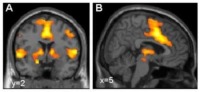

به گزارش روز شنبه گروه علمی ایرنا از پایگاه اینترنتی ساینس دیلی، محققان دانشگاه ورتسبورگ در آلمان با مطالعه روی بیش از پنج هزار داوطلب و 500 بیمار مبتلا به اختلال ترس، موفق شدند یک مسیر ژنتیکی برای ابتلا به چنین بیماری هایی را بیابند.

این محققان دستکم چهار واریان ژن GLRB را به عنوان عوامل خطرساز برای ابتلا به اختلالات اضطراب و ترس مشخص کردند.

در حال حاضر، اختلالات اضطراب با دارو و رفتار درمانی درمان می شود. اکنون محققان می گویند، کشف واریان های مختلف ژن GLRB که با اختلال های اضطراب ارتباط دارد، می تواند به ابداع درمان های پیشرفته تر کمک کند. آنها در نظر دارند که با استفاده از یافته های این مطالعه درمان های شخصی جدیدی را برای اختلالات اضطراب طراحی کنند.